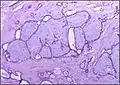

Histopathologic image of breast fibroadenoma. Core needle biopsy. Hematoxylin & eosin stain.

Histopathologic image of breast fibroadenoma showing proliferation of intralobular stroma compressing and distorting the epithelium. H&E stain.

Fibroadenoma of the breast is a benign tumor composed of a biplastic proliferation of both stromal and epithelial components.[12][13] This biplasia can be arranged in two growth patterns: pericanalicular (stromal proliferation around epithelial structures) and intracanalicular (stromal proliferation compressing the epithelial structures into slit-like spaces).

These tumors characteristically display hypovascular stroma compared to malignant neoplasms.[2][14][9] Furthermore, the epithelial proliferation appears in a single terminal ductal unit and describes duct-like spaces surrounded by a fibroblastic stroma. The basement membrane is intact.[15]